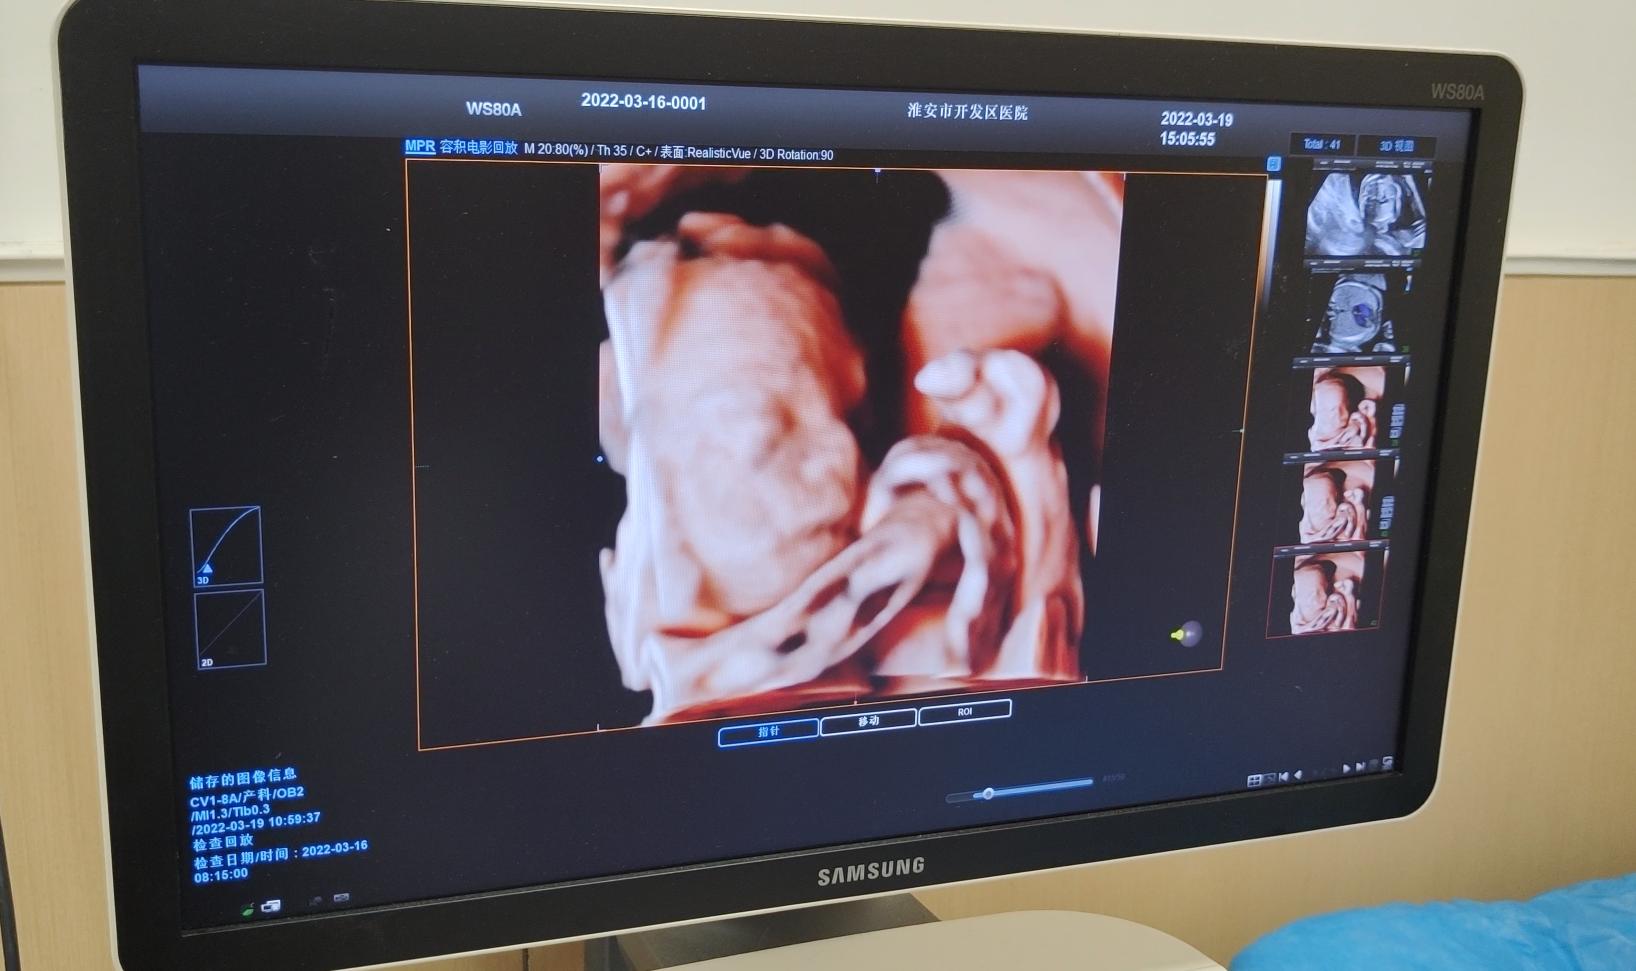

据悉,淮安经济技术开发区医院为更好的服务广大妇女,为他们提供一个温馨、周到、高效的医疗服务环境,医院引进了各种先进医疗设备,拥有全进口的核磁共振、CT、5D彩超、宫腹腔镜、产康康复仪、LEEP刀、新生儿辐射台、母儿监护仪、呼吸机、除颤仪等各种高新设备,可最大程度降低病人的手术风险与术中损伤,医院特有三星5D彩诊仪,可以获得更加立体的、逼真的图像,在排畸功能上更加完善,观察范围也更加广泛。